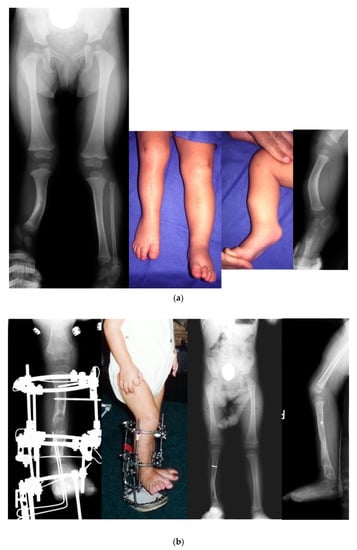

Figure 6.

(a) Preoperative radiographs and photographs of an 18-month-old girl born with Paley type 3a FH. She has fixed equinovalgus of the foot and a procurvatum-valgus diaphyseal tibial deformity. (b) Photograph (left) and radiograph (middle left) after the SUPERankle procedure combined with application of a circular external fixator for 5 cm of lengthening. Radiographs of the lower limbs after removal of the external fixator (right middle and right). (c) Photograph (left) and radiograph (middle) showing second lengthening of tibia at age 8, using computer dependent external fixator. She is shown doing pool therapy. Radiograph after removal of external fixator with correction of distal femoral valgus malalignment by hemiepiphysiodesis (right). (d) Radiograph showing the third and final lengthening of the tibia with lengthening of the femur both with external fixation at age 13. Radiograph after removal of the external fixators showing excellent alignment and equalization of limb lengths (middle). Final photograph at age 16 years after skeletal maturity with equal leg lengths and excellent function.